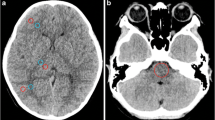

For each hemorrhage type, 20 cases were selected for qualitative analysis in which the respective hemorrhage type occurred in isolation in selected slices. Based on the results of the quantitative analysis, five specific VMIs (66 keV, 80 keV, 100 keV, 124 keV, 133 keV) were rated by five radiologists on a standard workstation: one experienced neuroradiologist with 15 years of experience, two general radiologists with 9 and 7 years of experience, and two residents with 4 and 2 years of experience, respectively. Those readers evaluated the delineation of the hemorrhage using a 5-point Likert scale (from 1 = “difficulty in delineating the bleeding, uncertain diagnosis” to 5 = “excellent delineation, fully diagnostic”). All readers were blinded to the keV level; every VMI was presented with equal standard windowing (C40/W80). Figure 2 shows the selection of VMI for the qualitative analysis, for reasons of illustration with two hemorrhage types, namely subarachnoidal and intraventricular hemorrhage.